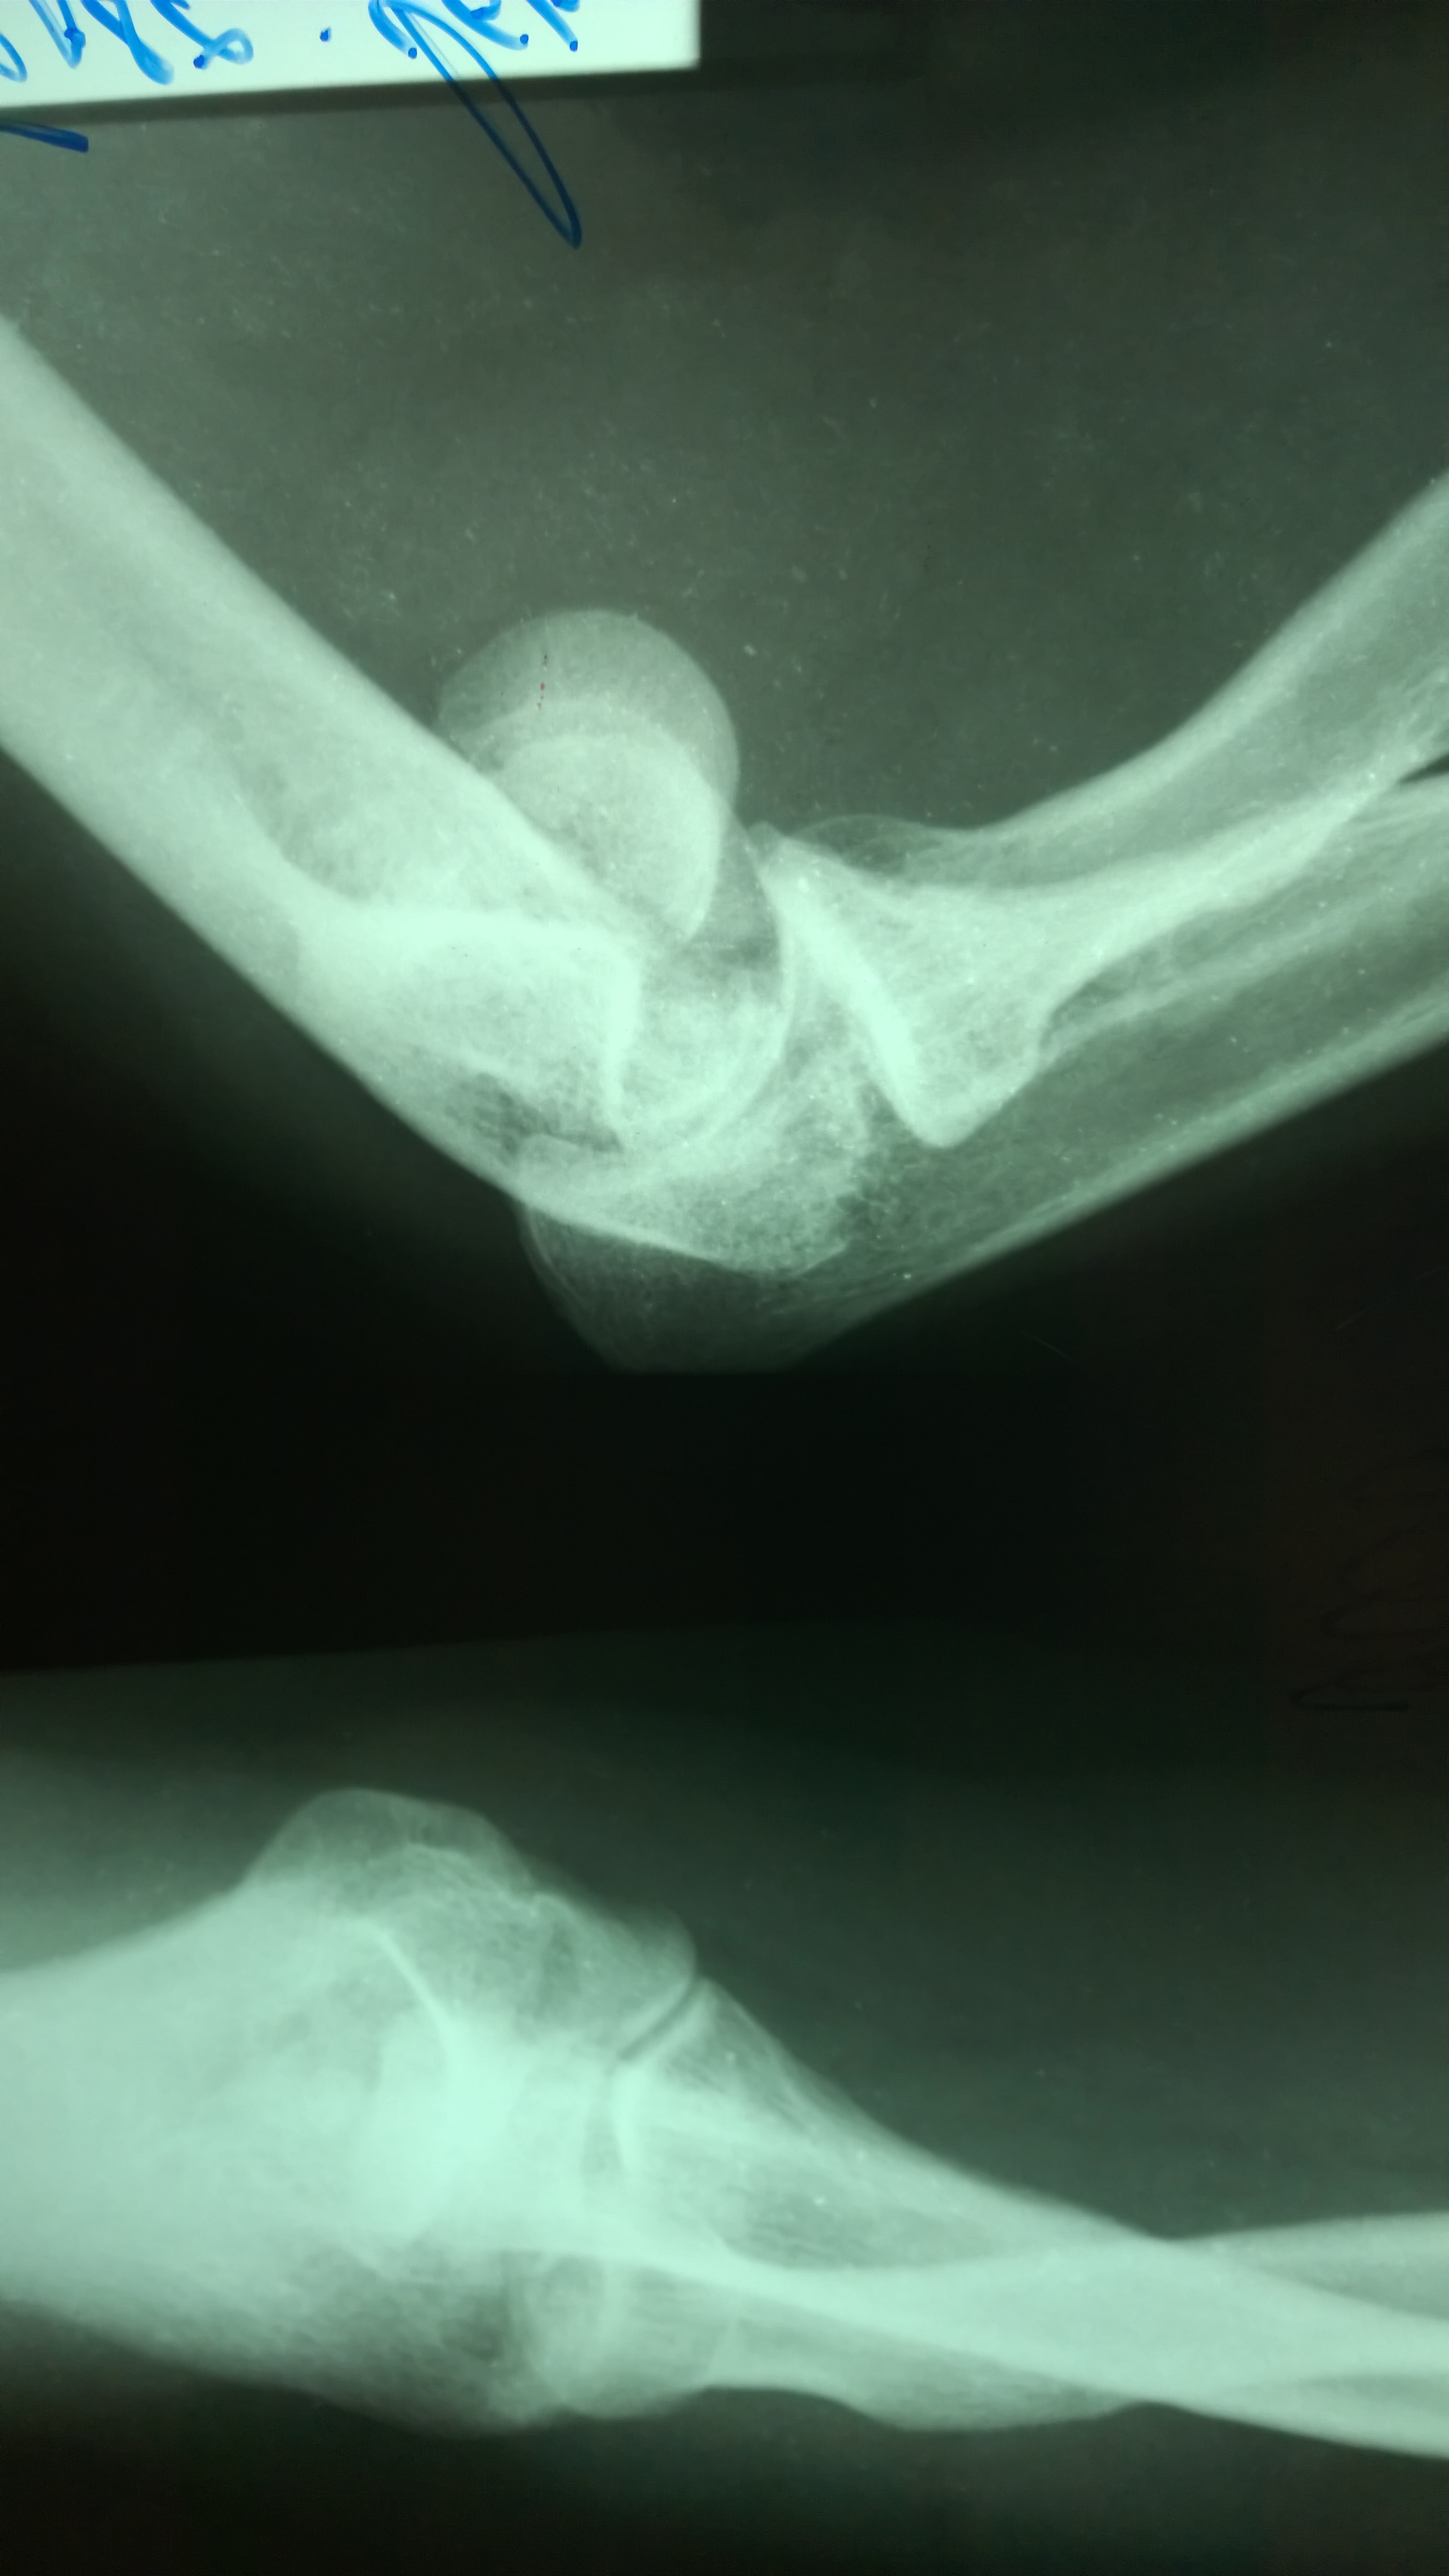

Закрытый перелом мыщелка плечевой кости